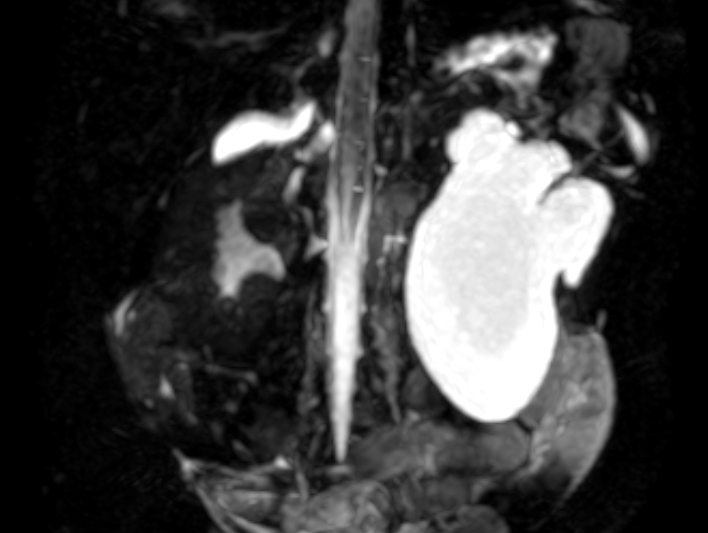

本次接受治疗的患儿,在出生前的产前B超检查中已被发现存在先天性左肾重度积水,出生满月后由地州医院转至新医大一附院就诊。入院检查显示,患儿左肾盂分离3.8CM,肾皮质最薄处0.16cm,核素肾动态显像检查提示左肾分肾功能下降大于20%。检查结果显示,孩子左肾形态和功能均受损明显,情况不容乐观,需要尽快手术。

患儿肾区影像